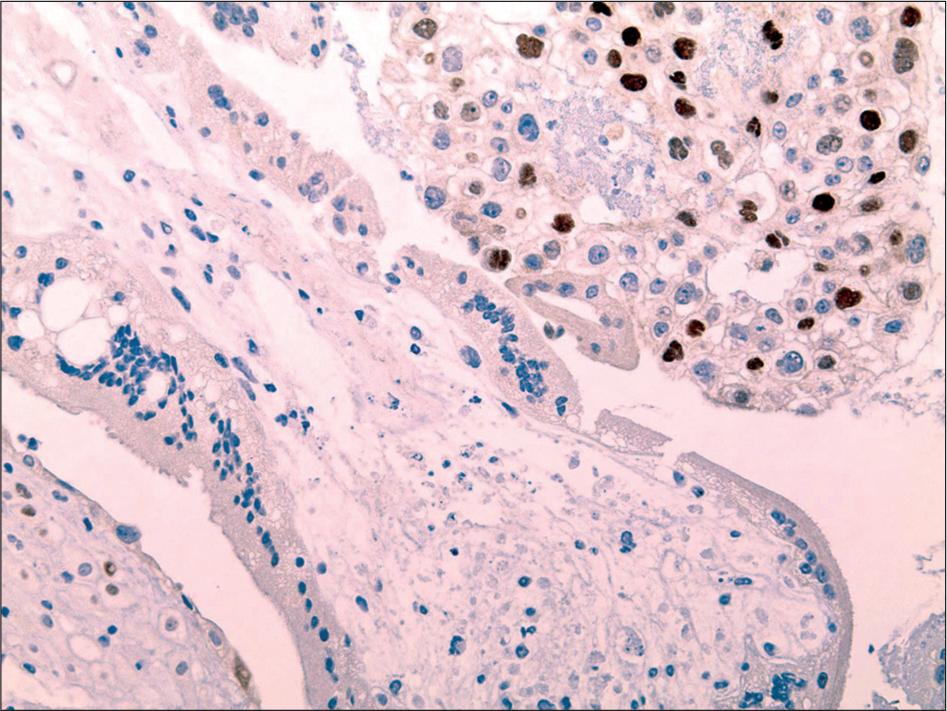

Immunohistochemical characteristics of complete moles_

| Positive Cells (%) | Ki-67 | p63 | p57 |

|---|---|---|---|

| n (%) | n (%) | n (%) | |

| 0 | 0 (0.0) | 0 (0.0) | 8 (100) |

| 10 | 0 (0.0) | 0 (0.0) | 0 (0.0) |

| 20 | 0 (0.0) | 0 (0.0) | 0 (0.0) |

| 30 | 0 (0.0) | 0 (0.0) | 0 (0.0) |

| 40 | 0 (0.0) | 0 (0.0) | 0 (0.0) |

| 50 | 0 (0.0) | 0 (0.0) | 0 (0.0) |

| 60 | 0 (0.0) | 3 (37.5) | 0 (0.0) |

| 70 | 4 (50.0) | 2 (25.0) | 0 (0.0) |

| 80 | 3 (37.5) | 3 (37.5) | 0 (0.0) |

| 90 | 1 (12.5) | 0(0.0) | 0 (0.0) |

| 100 | 0 (0.0) | 0(0.0) | 0 (0.0) |